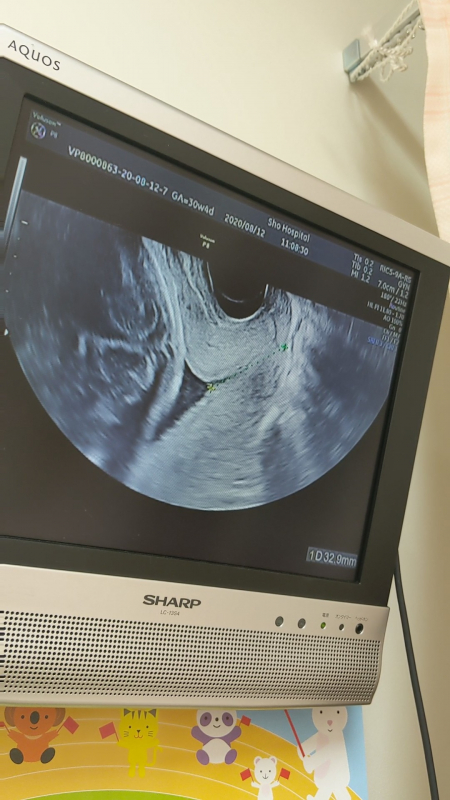

30週4日の健診で、少し柔らかくなっているけれど赤ちゃんが下がってきているわけではないこと、頚管長は32.9ミリとのことでした。